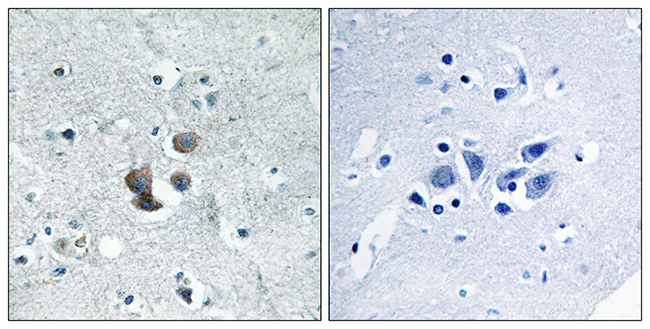

Anti-EGR3 AntibodyA97786

ApplicationsELISA, ImmunoHistoChemistry

ReactivityHuman, Mouse, Rat